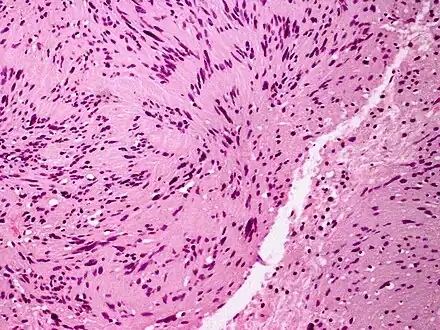

Palisaded and Encapsulated Neuroma